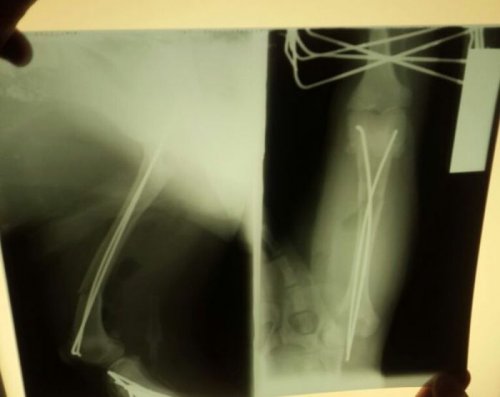

Ветеринары предложили усыпить доставленного пса, однако фонд настоял на спасении животного и проведении необходимой операции. Как оказалось, у него были переломаны задние лапы в семи местах, а также сломан крестец. Операция длилась в течение 8 часов, выставленный ветклиникой счёт составил 15.000 рублей. Операцию делали в долг, пока деньги на её оплату поступали на счёт фонда от неравнодушных Интернет-пользователей.